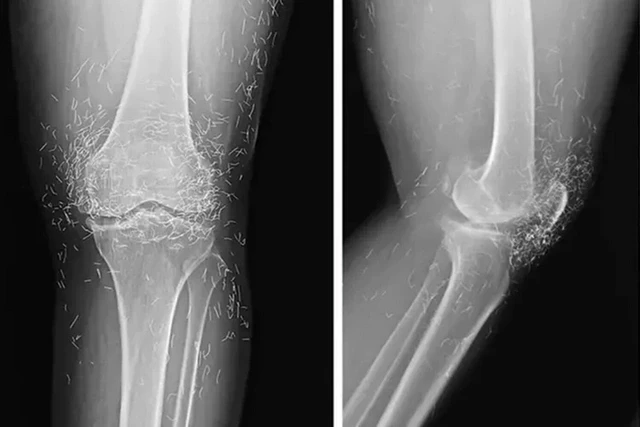

Rentgen müayinəsi zamanı sümüklərin qalınlaşması və deformasiyası, osteoartritin tipik əlamətləri, eləcə də diz oynağının ətrafındakı toxumaya yerləşdirilmiş yüzlərlə qızıl fraqmentlər müəyyən edilib.

Lent.az "Oddity Central"a istinadən xəbər verir ki, müayinə zamanı həkimlər gözlənilməz halla üzləşiblər - qadının ayaqlarında yüzlərlə xırda xalis qızıl sap aşkar edilib.